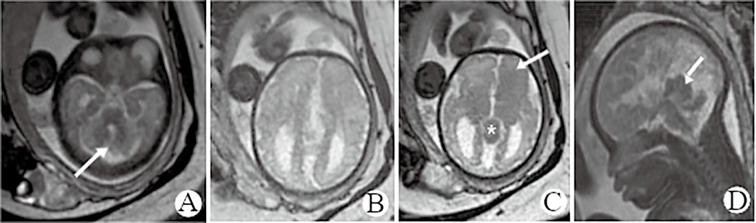

Clinical Observation on Orbital Teratoma of Delleman Syndrome Diagnosed by Fetal MRI Without Cutaneous Manifestations.